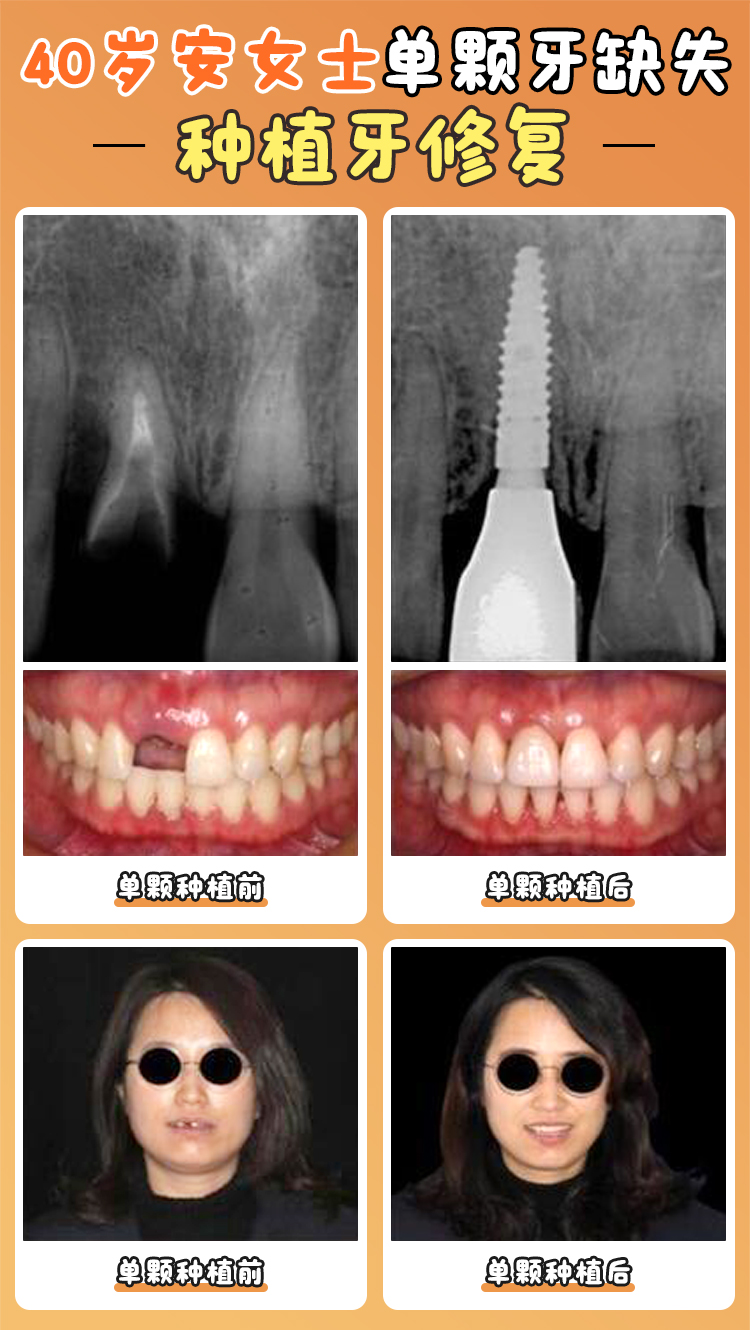

臨床經(jīng)驗:在種植牙方面,醫(yī)生們能夠熟練掌握多種種植技術(shù)和新型的種植系統(tǒng),能夠根據(jù)不同患者的口腔條件,如牙槽骨密度、牙齒缺失情況等,制定個性化的種植方案。無論是單顆牙缺失、多顆牙缺失還是一口牙缺失,都能提供有效解決方案。在牙齒矯正方面,醫(yī)生們也有豐富的經(jīng)驗,能夠根據(jù)患者的具體情況,選擇合適的矯正方法,如金屬托槽矯正、隱形矯正等。

種植牙成效:不少患者在焦作植得口腔醫(yī)院進(jìn)行種植牙后,都取得了滿意的成效。例如,一位60多歲的老大爺,由于牙齒缺失多年,生活受到了較大影響。在焦作植得口腔醫(yī)院進(jìn)行了種植牙手術(shù),術(shù)后修復(fù)良好,能夠正常咀嚼食物,生活質(zhì)量得到了較大提高。他表示,醫(yī)生技術(shù)不錯,手術(shù)過程中幾乎沒有疼痛感,術(shù)后也沒有出現(xiàn)任何不適。